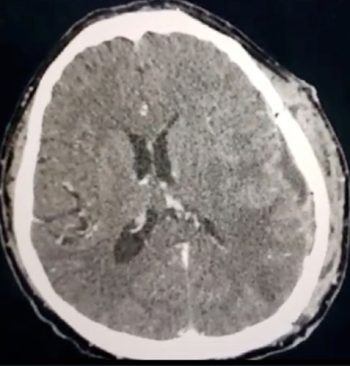

• Tumores cerebrales

• Hematomas (coágulos) Intracraneales: Epidurales y subdurales

• Hidrocefalias

• Alteraciones vasculares cerebrales

• Evento vascular cerebral (hemorragias)